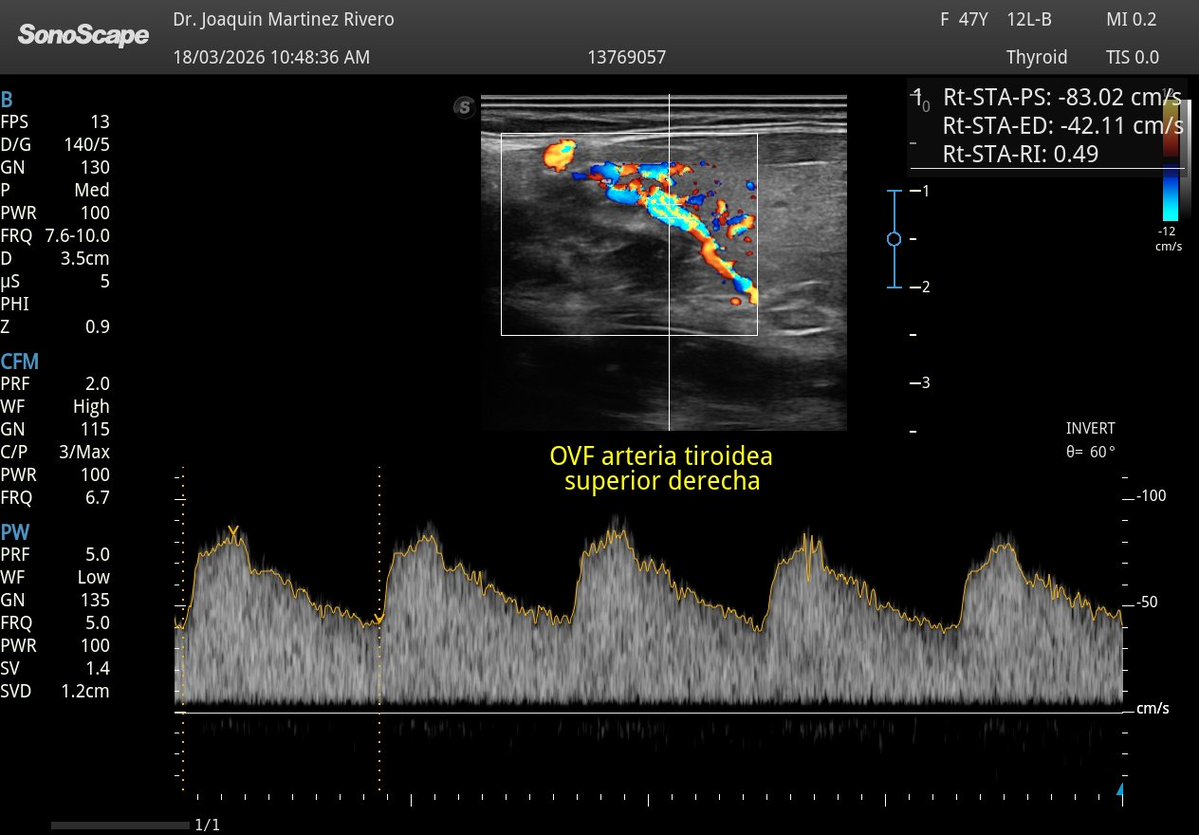

@2495Semper @Rad_Munagi @JMMR83 Cómo buen radiólogo: Hipervascularización tiroidea en Doppler (VPS 83 cm/s), hallazgo sugestivo de Enfermedad de Graves en contexto clínico adecuado. Correlacionar con perfil hormonal y anticuerpos tiroideos. 😂😂

Una de las cosas que más he notado con la mejora de nuestro equipo es la calidad del doppler, ¡qué diferencia!